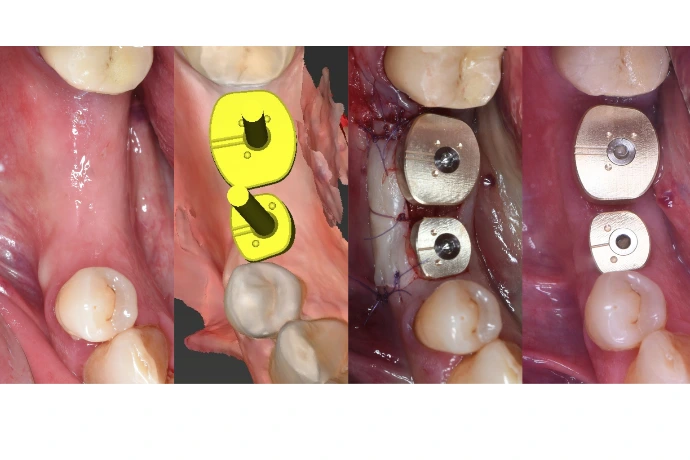

Préservation alvéolaire, régénération osseuse simple et optimisation mucogingivale.

TP : lambeaux, greffes conjonctives et épithélio-conjonctives sur mâchoires animales, ROG péri-implantaire.

Module 4 – Centre Orosanté (Grésy-sur-Aix)

L’implantologie simple, passer le pas